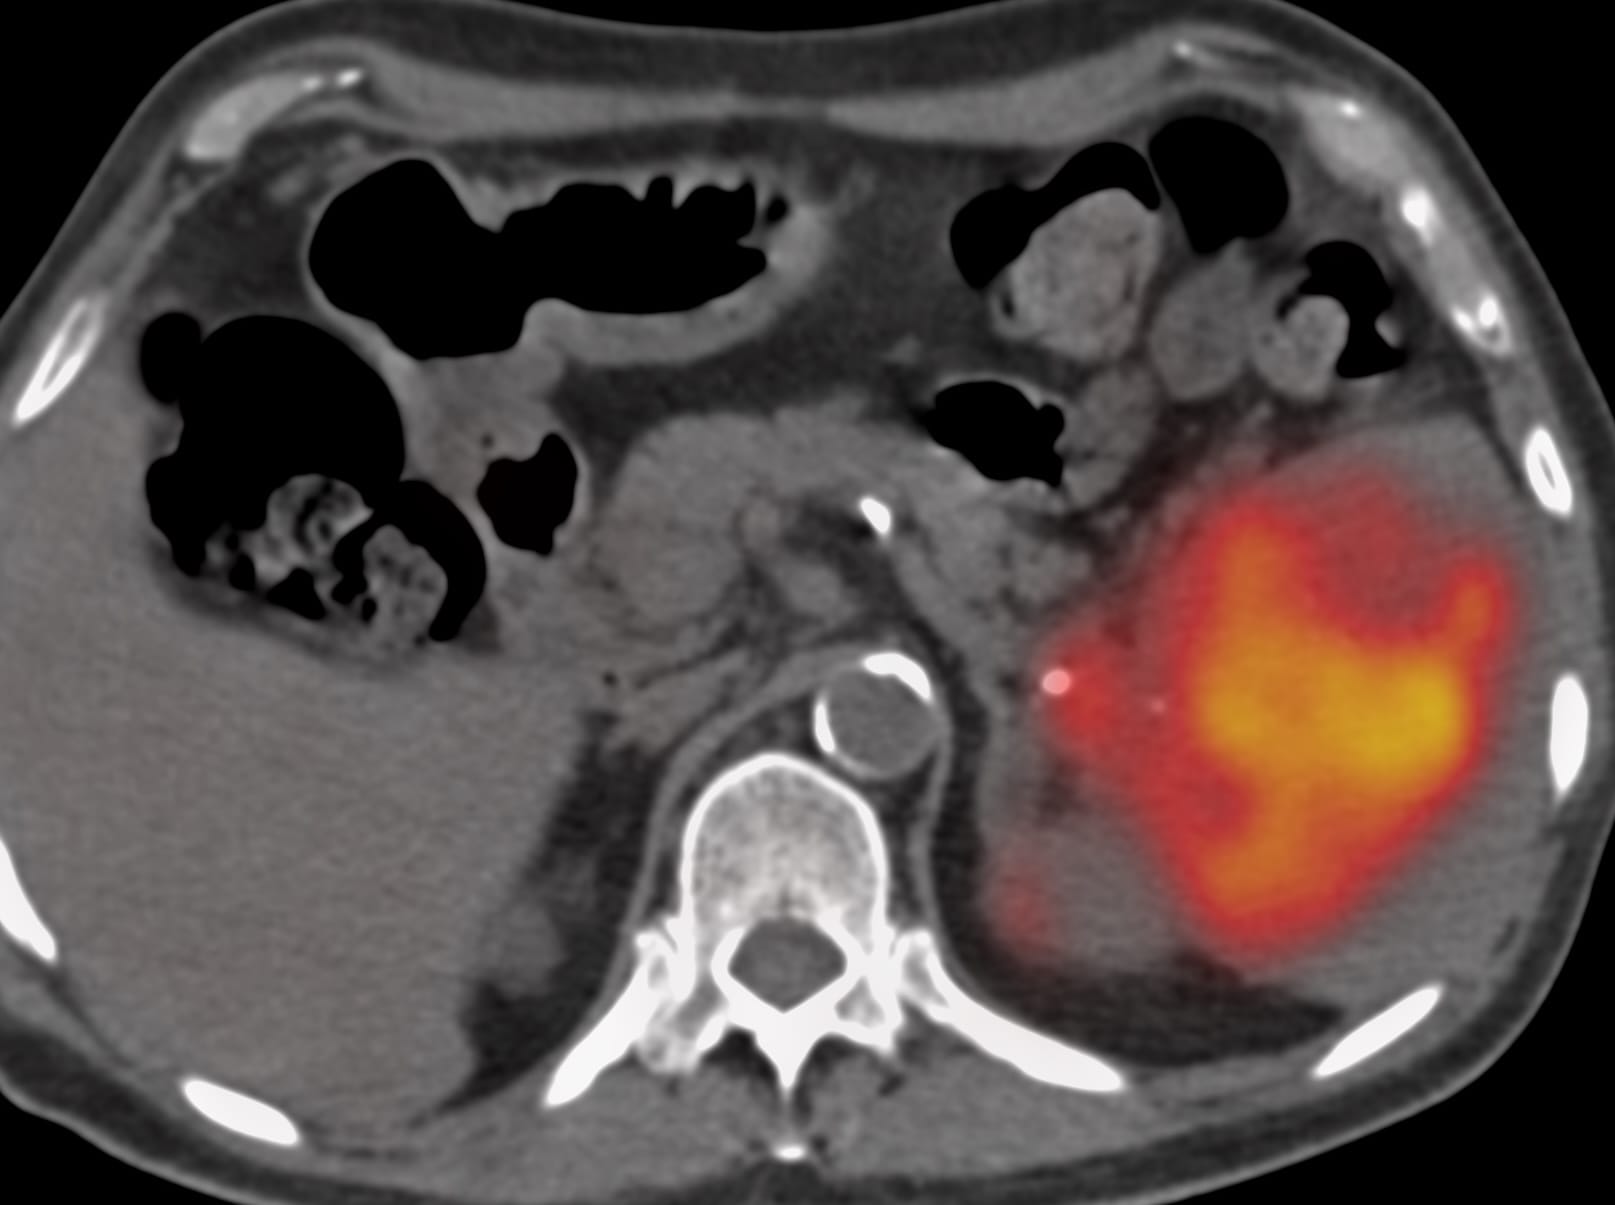

66-years old man presented with a mass in the spleen involving the tail of the pancreas.

The patient came for a biopsy and I decided to use an anterior approach in the supine position.